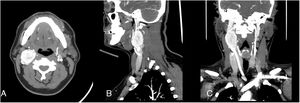

La cirugía se inició realizando una incisión en cara anterior del esternocleidomastoideo derecho, diseccionando a través de los planos hasta identificar la arteria carótida común y sus ramas interna y externa, junto al tumor que las envolvía. En el procedimiento, se observó adenopatía submandibular derecha de 2cm, que fue enviada a biopsia diferida. Se exponen los extremos proximal y distal de las arterias y se identifican los nervios vago, hipogloso, laríngeo superior y se apartan del tumor, para luego resecar el tumor en el plano subadventicial mediante electrocauterización bipolar. El tumor fue resecado completamente (fig. 2), respetando estructuras vasculares y nerviosas adyacentes, con hemostasia adecuada. Se comprobó el flujo carotídeo con ecografía Doppler, se colocó un drenaje por el borde caudal de la incisión y se cerró la incisión.

Para la cirugía se realizó una incisión por el borde anterior del esternocleidomastoideo derecho, disecando los planos hasta exponer el paquete vasculonervioso. Se expuso la vena yugular interna y se diseccionó por su borde medial. Se ligaron las venas lingual y facial, lateralizando la vena yugular hasta identificar la arteria carótida común y el nervio vago e hipogloso, apartándolos del tumor. Se identificó el tumor y se procedió a realizar la resección subadventicial mediante electrocauterización bipolar, requiriendo seccionar un asa del nervio hipogloso por su adherencia al tumor. Se logró la resección completa del tumor (fig. 4), con hemostasia adecuada. Para finalizar se comprobó flujo con ecografía Doppler y se dejó un drenaje por el borde caudal, cerrando la incisión.